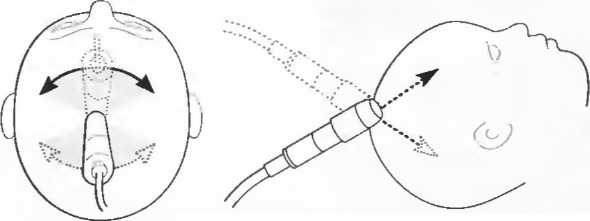

3. Ультразвуковые исследования в педиатрии. Для детей необходим датчик с частотой 5 МГц с глубиной фокусировки на 5-7 см. При исследовании мозга новорожденного используется секторный датчик с частотой 7,5 МГц с глубиной фокусировки на 4-5 см (этот датчик также используется для исследования яичек и структур шеи у взрослых).